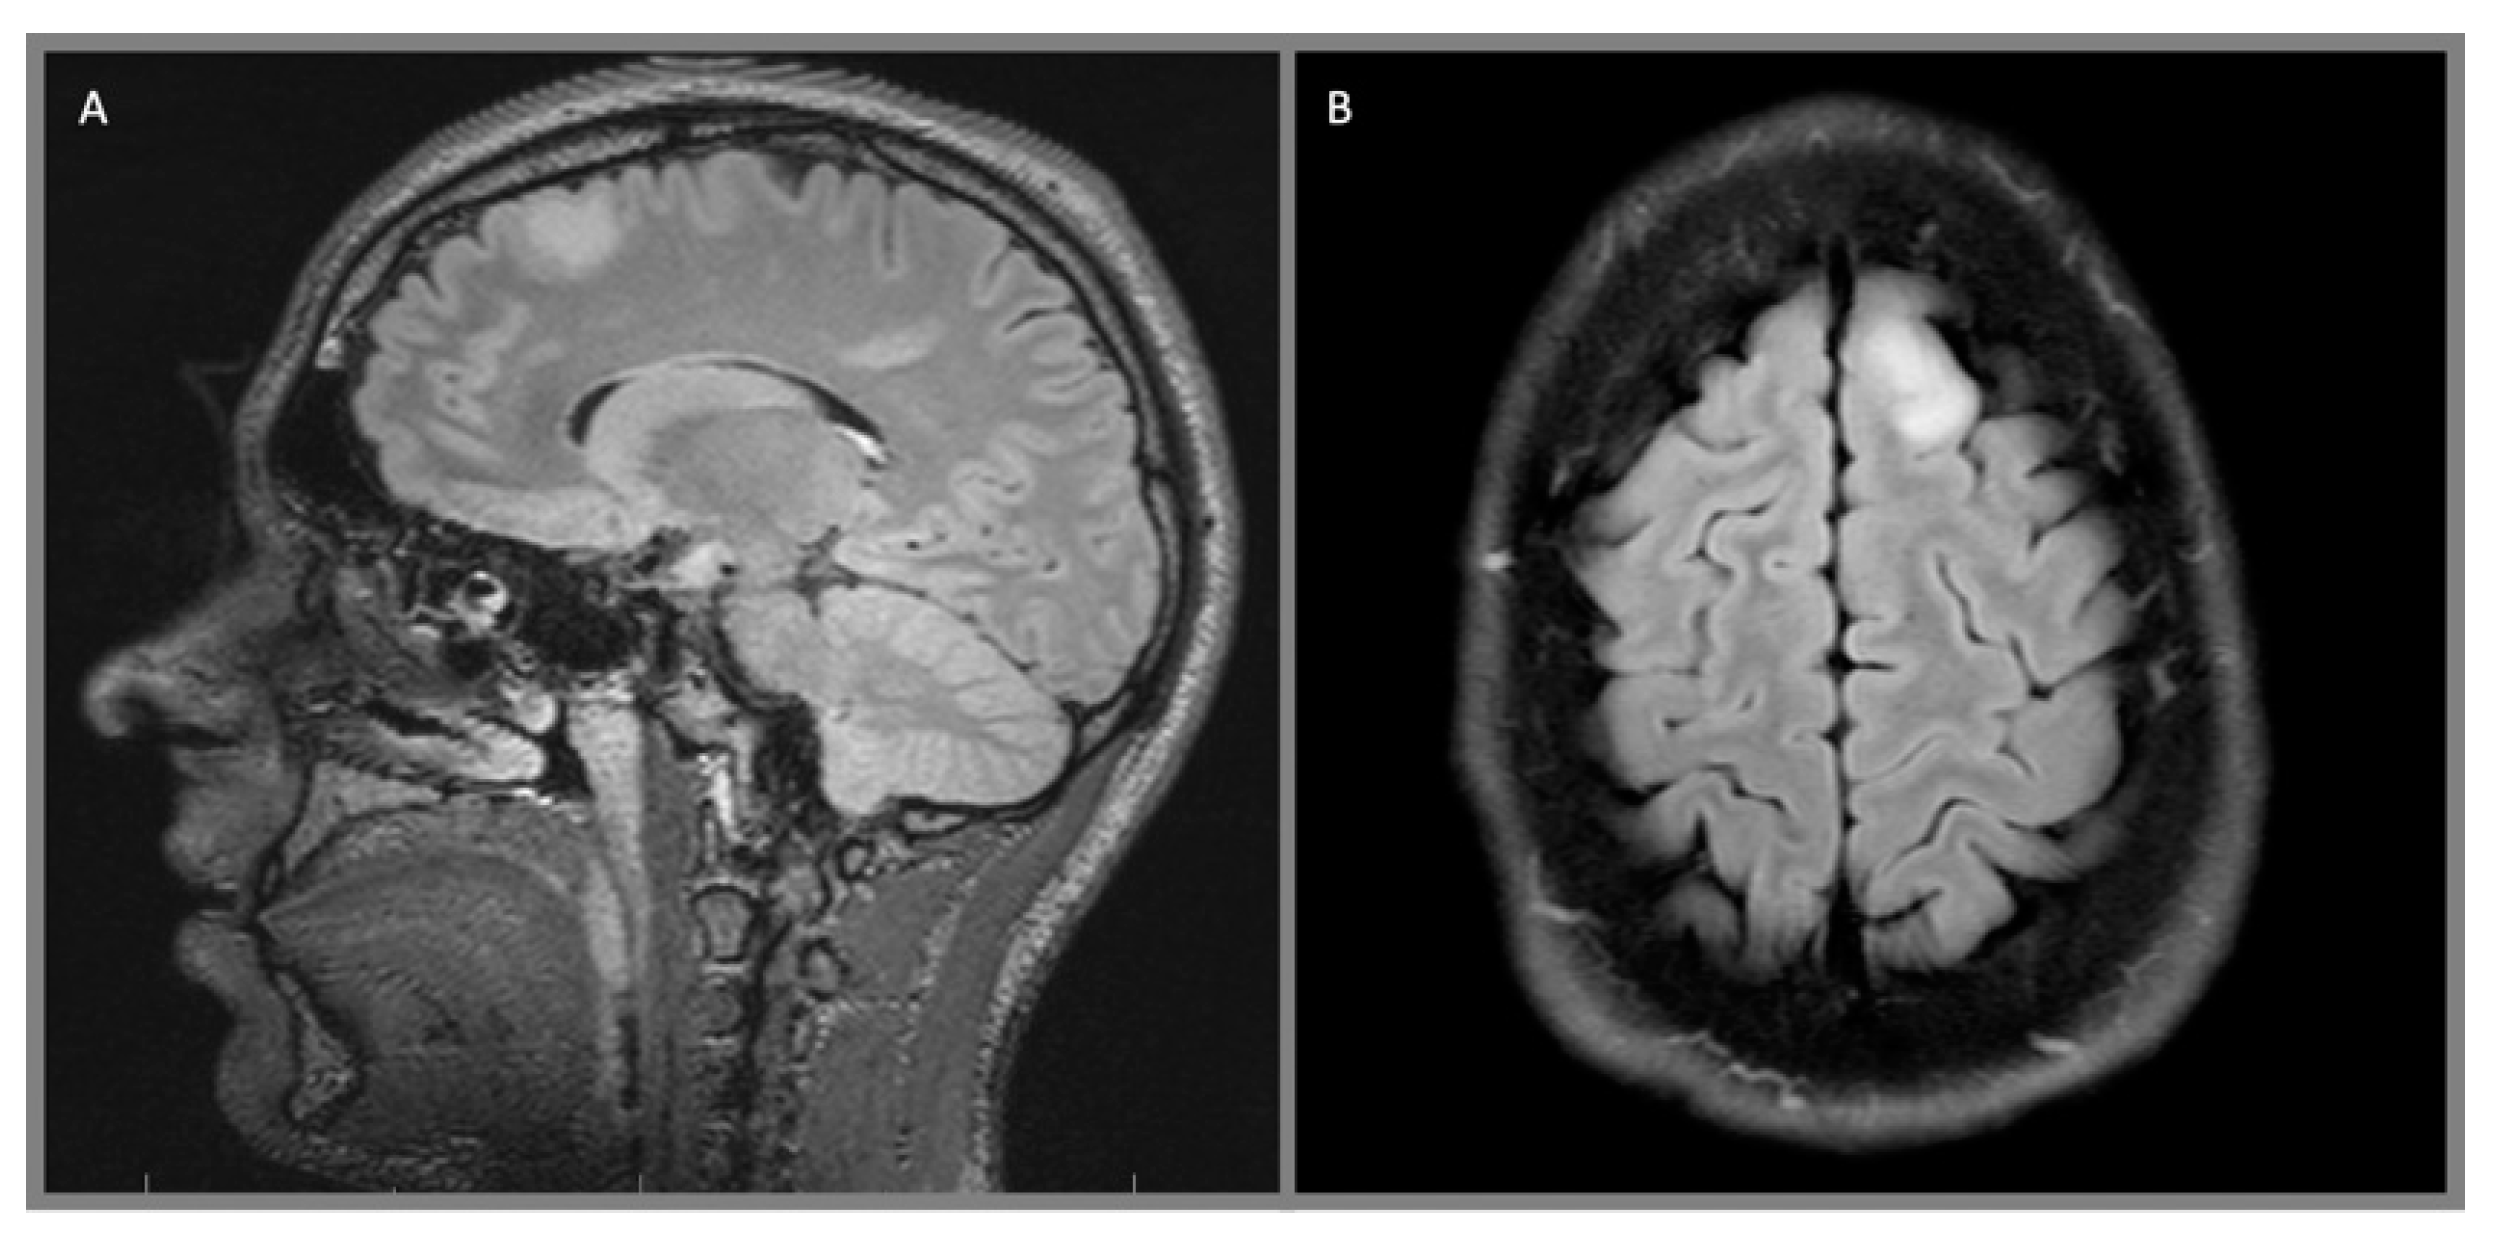

4. Diagnostic Studies